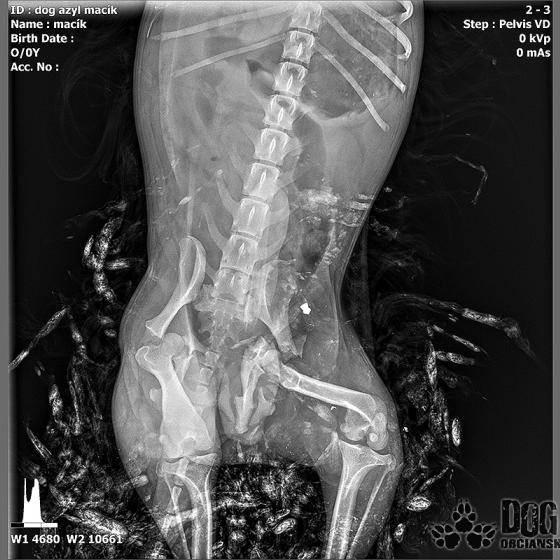

Vianoce nám klopú na dvere a mali by to byť sviatky radosti a pokoja. No u nás nebudú a pre malého Jamesa už vôbec nie. Malého Jamesa sme prijali s mnohonásobnými fraktúrami panvy. Presnejšie, s obojstrannou iliosakrálnou luxáciou/fraktúrou, viacnásobnou fraktúrou panvy, vrátane fraktúry kranialneho acetabula obojstranne. Áno, znie to hrozivo a keď si pozriete snímky z RTG, bude to ešte hrozivejšie (ďalšie snímky ešte doplníme).

Čakali ho teda štyri, veľmi náročné ortopedické operácie, takže sa musel trocha posilniť. Do starostlivosti si ho vzala MVDr. Panyi Terzieva a 17.11. mohol absolvovať prvú operáciu. V "prvom kole" krpec zvládal anestézu tak dobre, že sa rovno mohli spojiť dve operácie a tak sa celá ľavá strana dala do poriadku. Zostal samozrejme naďalej hospitalizovaný. Ďalší zákrok sa naplánoval na 20.11. a našťastie opäť všetko prebehlo hladko, a zoperovala sa celá pravá strana(nechceme sa dlho rozpisovať, prikladáme lekársku správu). James bol prepustený 24.11. ako chodiaci pacient a bez problémov ovládal aj vylučovanie! Je to priam zázrak, za ktorý opäť vďačíme MVDr. Vatolíkovi a jeho teamu.